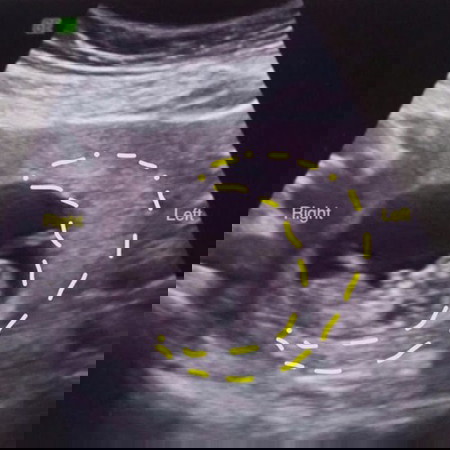

Congenital Anomaly Scan

Hello mommies usually anong buwan po ba pinapagawa ung CAS? Going to 6mos plng po ako nexth month pero papagawa na po skin ung cas pagbalik ko next check up.

Nag research ako dati, 18-22 weeks, 4-5 months.

24 weeks.